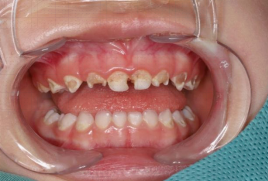

▲术前口内照片

患儿三岁,口腔内有多颗龋坏牙需要治疗,因年龄太小畏惧环境抗拒治疗。经专家团队的综合评估制定了适宜的镇静镇痛方案,在征得患儿父母同意后,开展了全麻下儿童口腔舒适化治疗,让患儿在轻松、舒适的状态下一次性成功完成龋齿、牙髓病及根尖周病等共计14颗龋坏牙的治疗。治疗后患儿状态良好,家长对治疗效果表示满意。